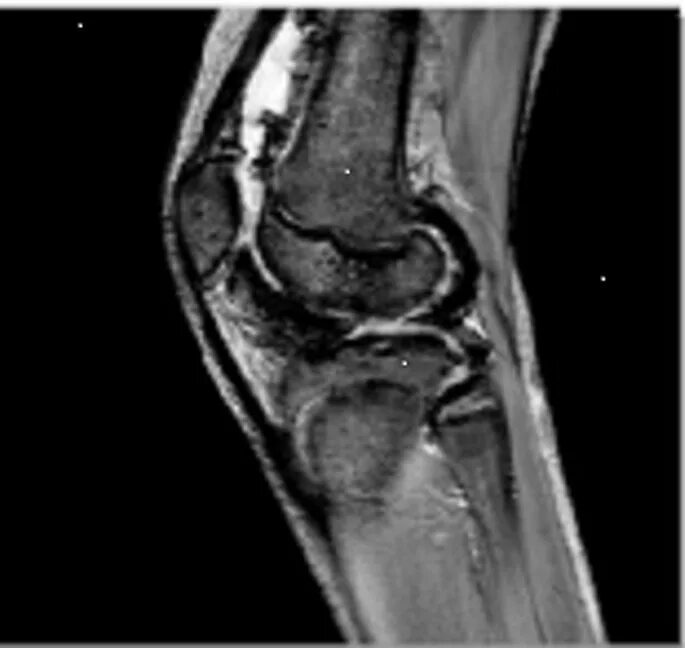

Пигментный виллонодулярный синовит